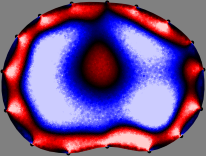

Refer to caption

Figure 2: Fidelity-embedded regularization method. (Left bottom) Correlations between four different column vectors (𝐒ksubscript𝐒𝑘{\bf S}_{k}) and all the remaining column vectors (𝐒subscript𝐒{\bf S}_{\ell}) are visualized. (Right bottom) Performances of the proposed fidelity-embedded regularization method for λ=𝜆\lambda=\infty are shown by numerical simulations.

To explain the FER method, we closely examine the correlations among column vectors of the sensitivity matrix 𝕊𝕊\mathbb{S}, described in Fig. 2. The correlation between 𝐒ksubscript𝐒𝑘{\bf S}_{k} and 𝐒subscript𝐒{\bf S}_{\ell} can be expressed as

for i=1,,16𝑖116i=1,\cdots,16[23]. This shows that the column vector 𝐒ksubscript𝐒𝑘{\bf S}_{k} is like an EEG (electroencephalography) data induced by dipole sources with directions uj,j=1,,16formulae-sequencesubscript𝑢𝑗𝑗116\nabla u_{j},j=1,\cdots,16 at locations ΔksubscriptΔ𝑘\Delta_{k}. Given that two dipole sources at distant locations produce mutually independent data, the correlation between 𝐒ksubscript𝐒𝑘\mathbf{S}_{k} and 𝐒subscript𝐒\mathbf{S}_{\ell} decreases with the distance between ΔksubscriptΔ𝑘\Delta_{k} and ΔsubscriptΔ\Delta_{\ell}. Fig. 2 shows a few images of the correlation 𝐒k,𝐒(|𝐒k||𝐒|)1subscript𝐒𝑘subscript𝐒superscriptsubscript𝐒𝑘subscript𝐒1\left\langle\mathbf{S}_{k},\mathbf{S}_{\ell}\right\rangle(|\mathbf{S}_{k}||\mathbf{S}_{\ell}|)^{-1} as a function of \ell for four different positions ΔksubscriptΔ𝑘\Delta_{k}. The correlation decreases rapidly as the distance increases. In the green regions where the correlation is almost zero, 𝐒subscript𝐒{\bf S}_{\ell} is nearly orthogonal to 𝐒ksubscript𝐒𝑘{\bf S}_{k}.